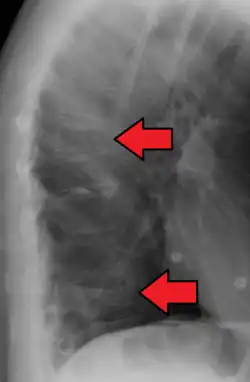

A compression fracture is a collapse of a vertebra. It may be due to trauma or due to a weakening of the vertebra (compare with burst fracture). This weakening is seen in patients with osteoporosis or osteogenesis imperfecta, lytic lesions from metastatic or primary tumors,[1] or infection.[2] In healthy patients, it is most often seen in individuals suffering extreme vertical shocks, such as ejecting from an ejection seat. Seen in lateral views in plain x-ray films, compression fractures of the spine characteristically appear as wedge deformities, with greater loss of height anteriorly than posteriorly and intact pedicles in the anteroposterior view.[3]

Compression fracture of the fourth lumbar vertebra post falling from a height. -

Compression fracture of T12